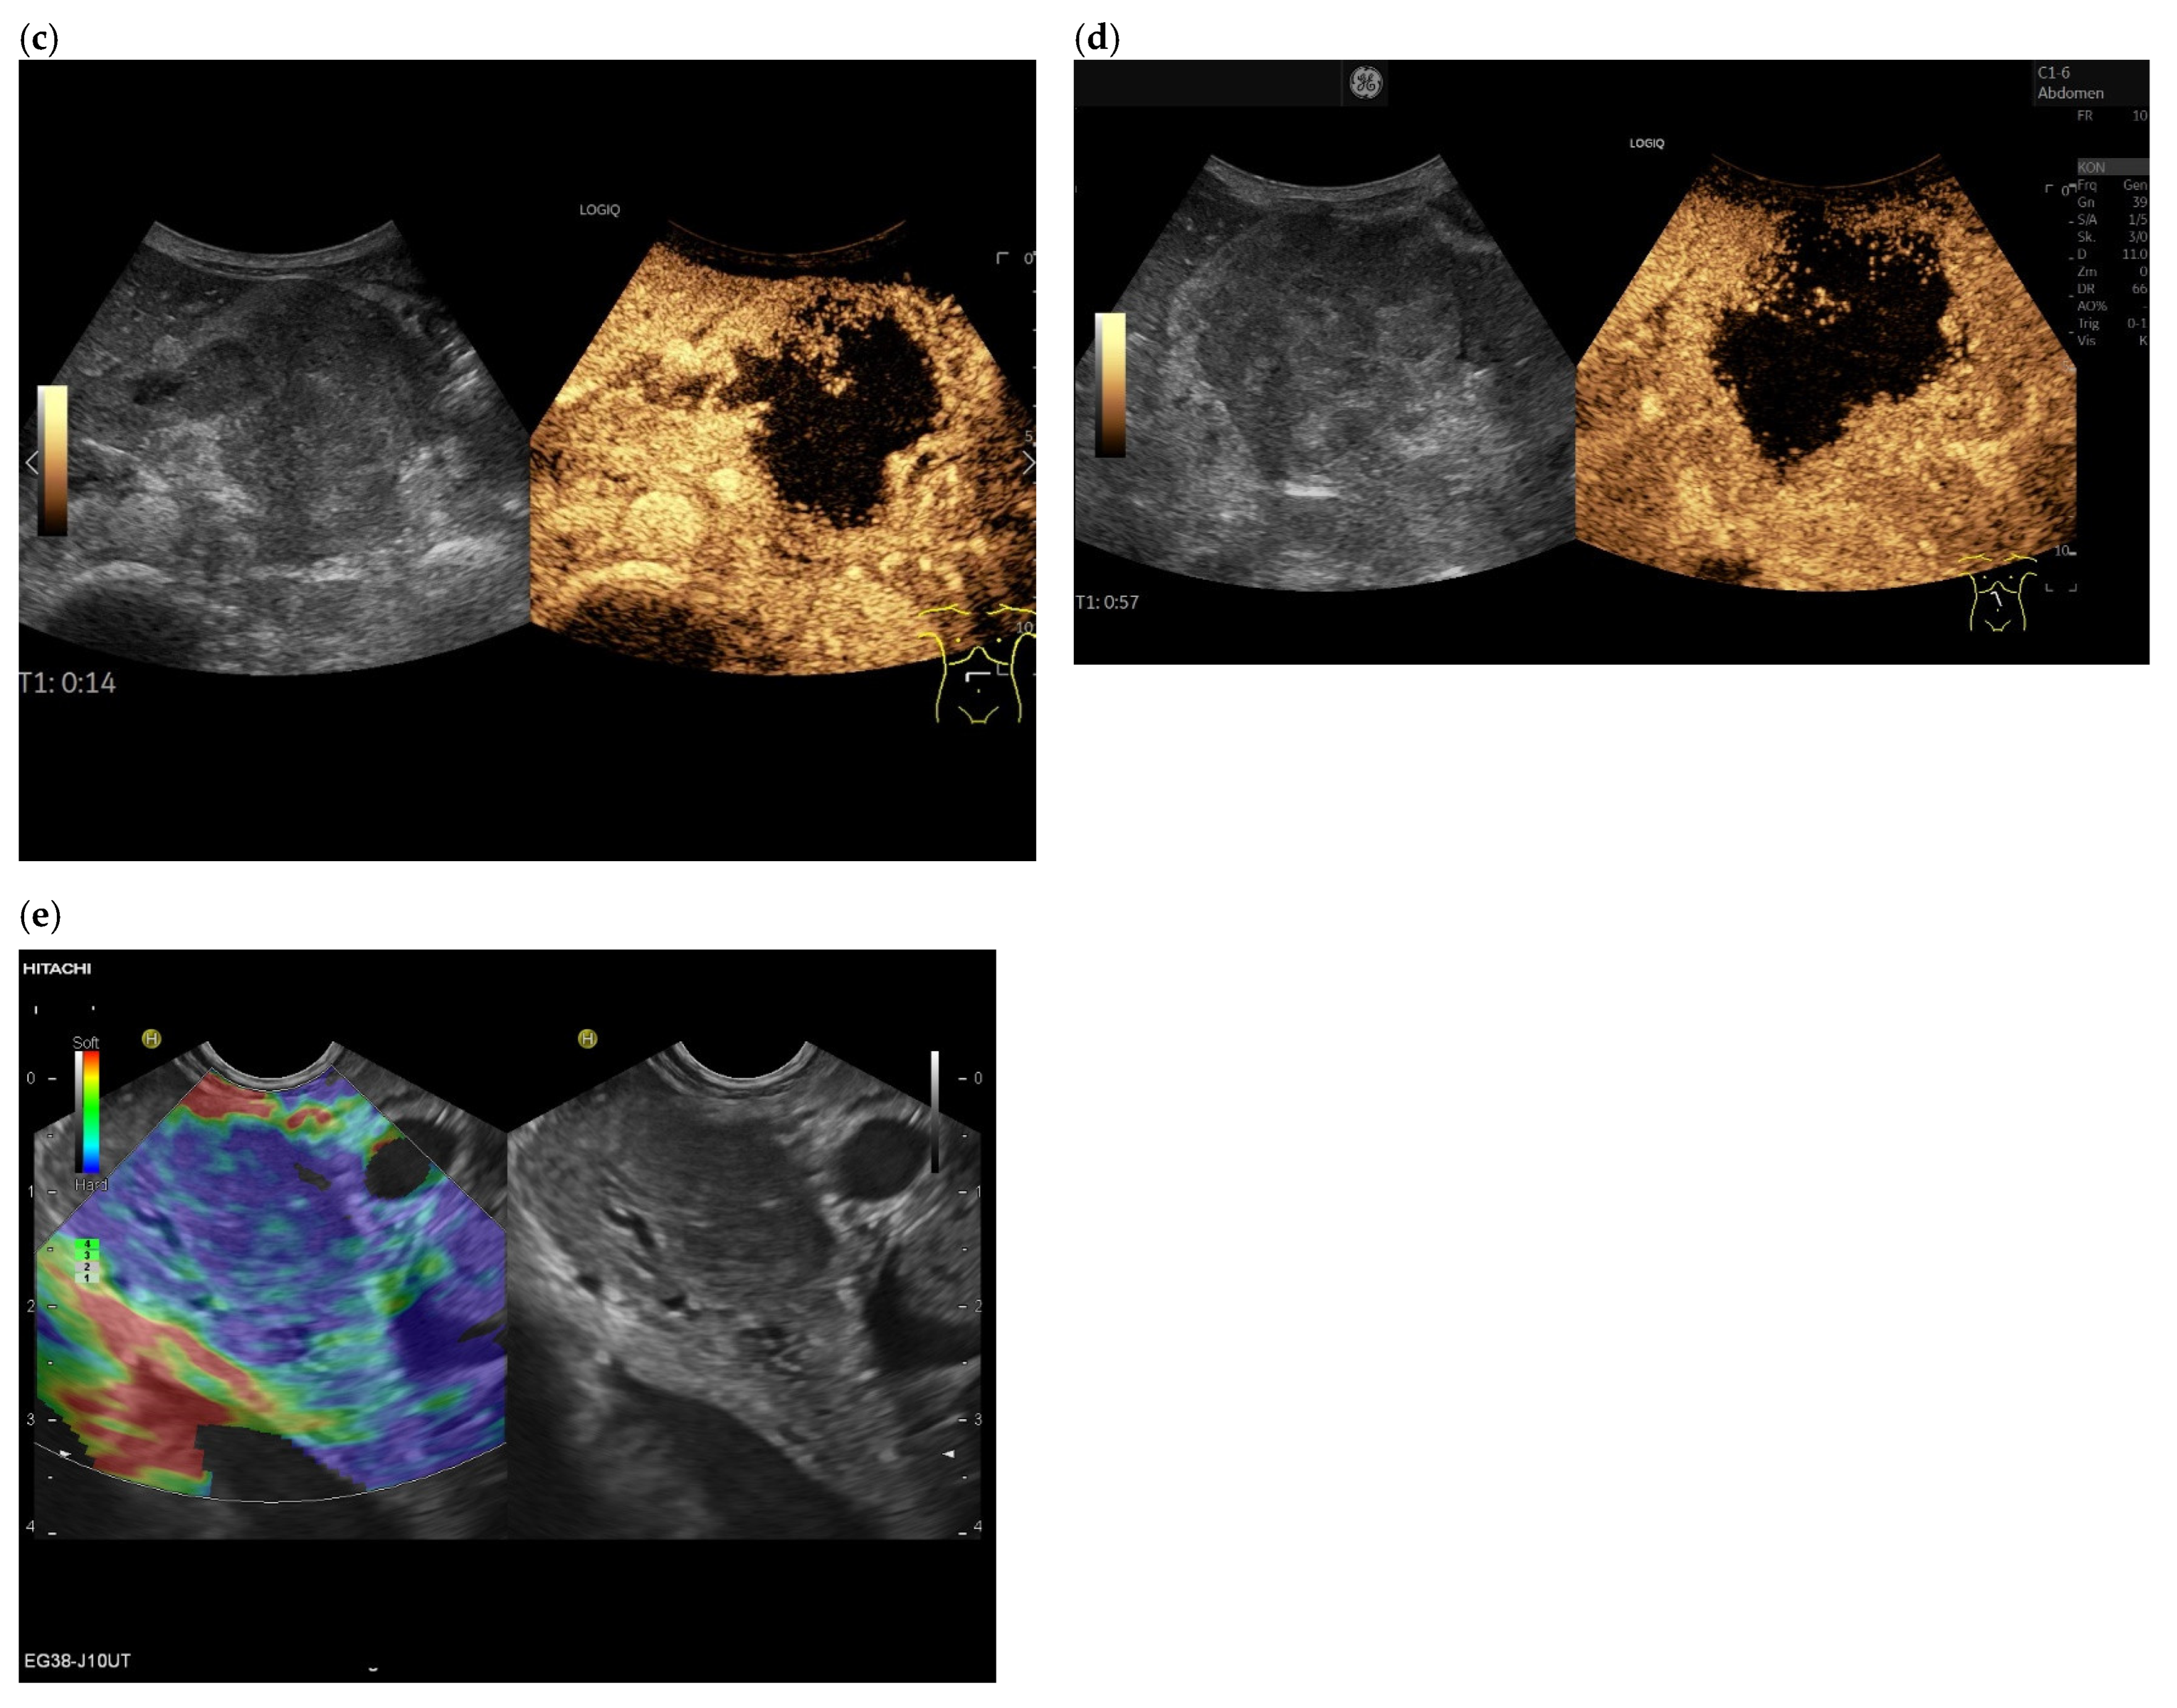

3.4. CEUS and CH-EUS

| RCC metastases [83] (n = 4) | Hyperenhancement, Early | Hyperenhancement | ||

| RCC metastases [61] (n = 3) | Hyperenhancement, homogeneous pattern | Slow washout | ||

| RCC metastasis [86] (n = 1) | Hyperenhancement, Inhomogeneous pattern | No washout | ||

| Melanoma metastasis [63] (n = 1) | Iso- to slightly hypoenhanced | Hypoenhanced | ||

| Melanoma metastasis [87] (n = 1) | Isoenhanced | Hypoenhancement of the peripheral rim, central non-enhancement | ||

| Melanoma metastasis [61] (n = 1) | Isoenhanced, heterogeneous | Fast washout | ||

| SCLC metastasis [83] (n = 1) | Hyperenhancement | Rapid washout | ||

| Breast, ovarian, colon metastases, sarcoma metastases [61] (n = 6) | Hypoenhancement, homogeneous or heterogeneous | Fast or slow washout | ||

| Lymphoma metastasis [61] (n = 1) | Hyperenhancement, homogeneous pattern | Fast washout |